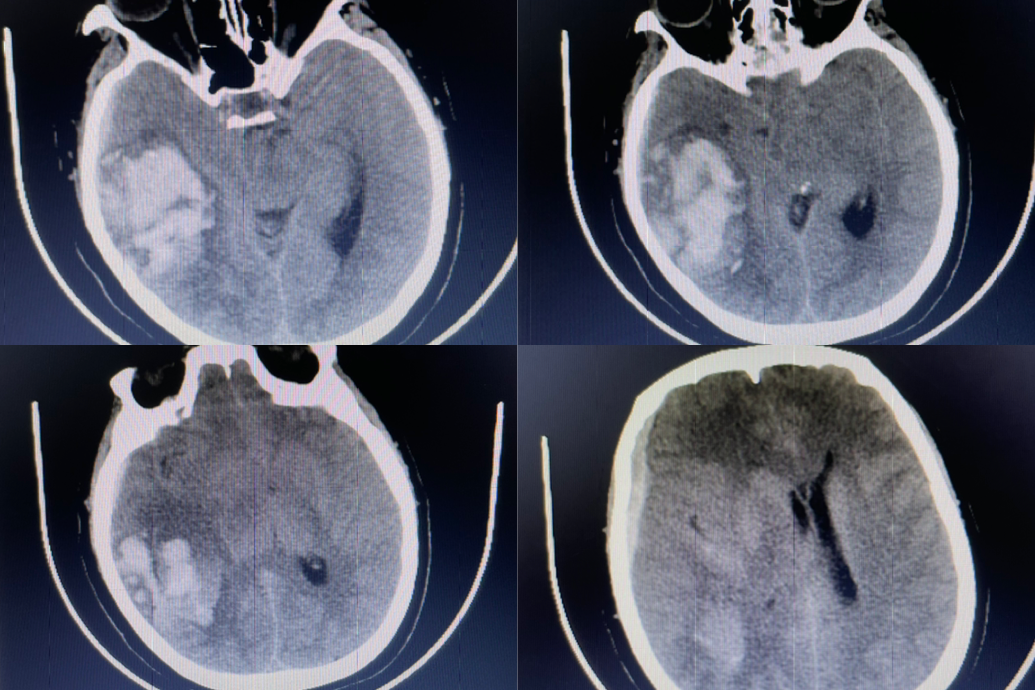

术后第一天复查